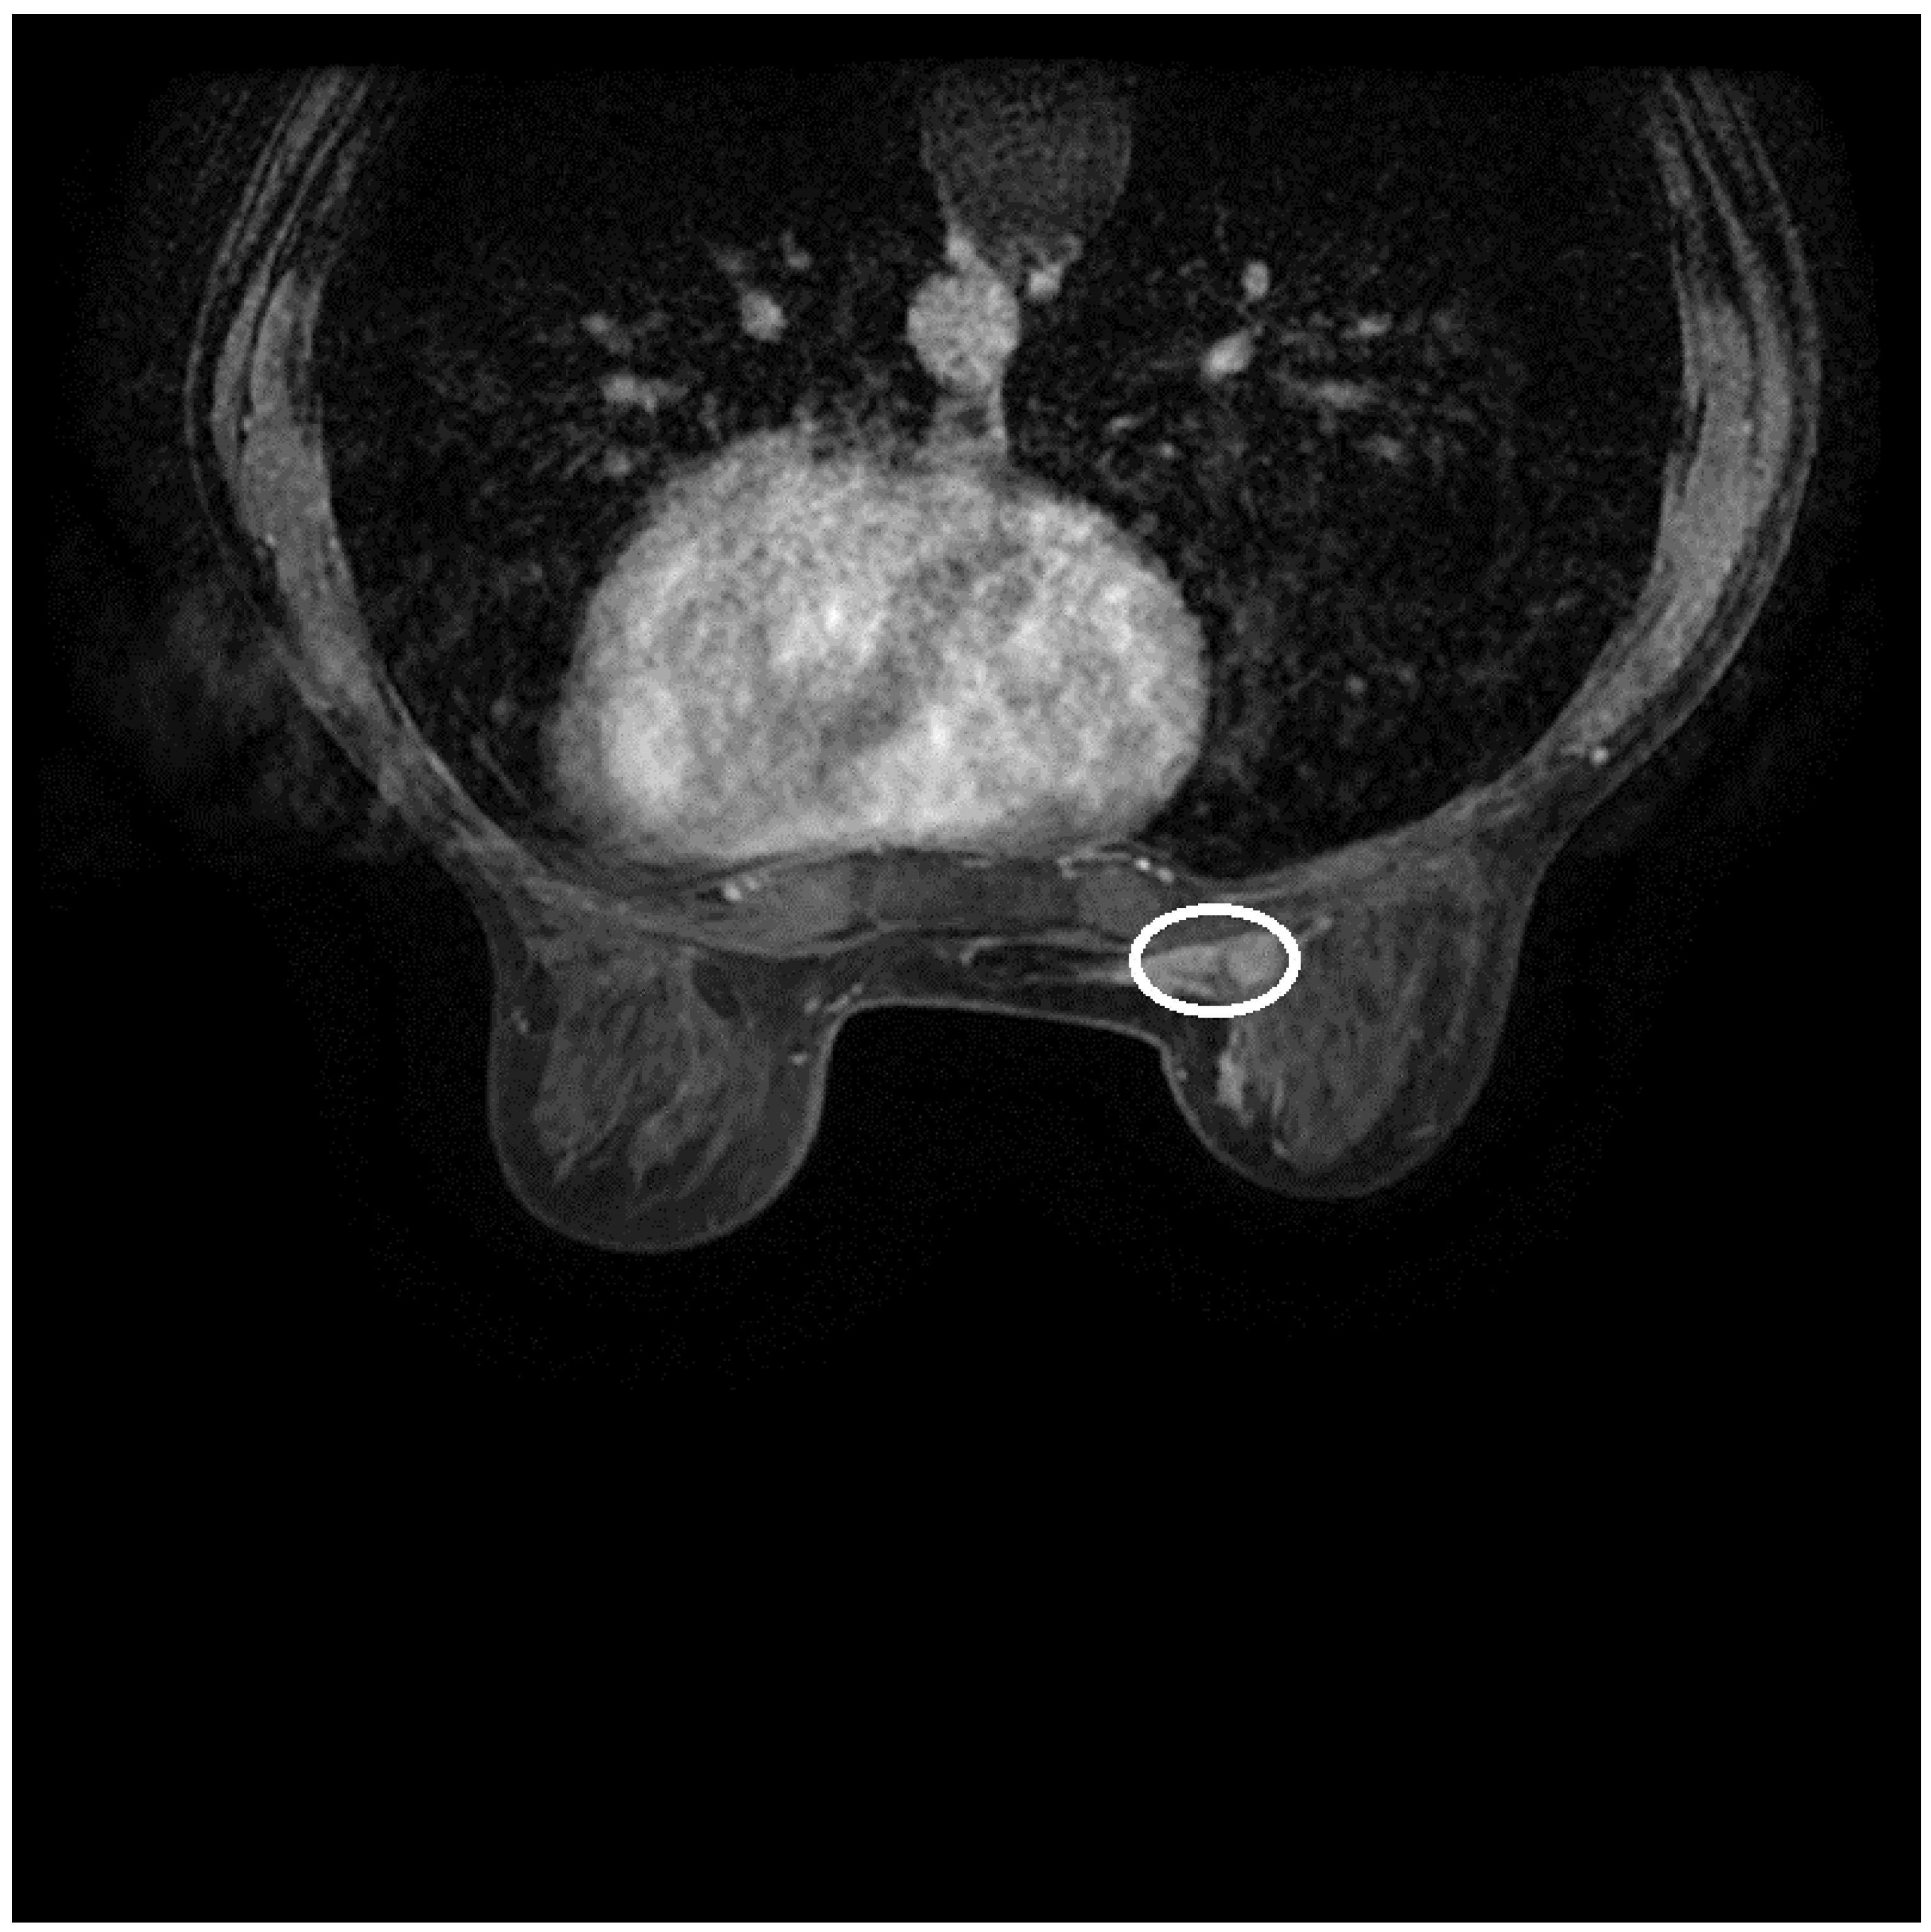

2.2. Imaging